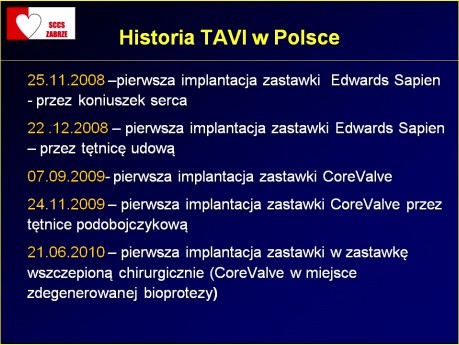

Prof. Marian Zembala - Polski rejestr TAVI

Polski rejestr TAVI - miejsce dla kardiologa inwazyjnego i kardiochirurga. Prof. dr hab. n. med. Marian Zembala - dyrektor ŚCCS w Zabrzu przedstawia polskie doświadczenia w zabiegach TAVI. TAVI to...